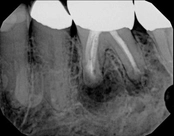

Lower molar failed root canal, microsurgery saved the tooth:

Before

Immediately after

3-month follow-up with complete healingThis patient presented with a failed root canal. The root canal became infected. An apicoectomy (apical microsurgery) was performed using the laser. Patient had minimal swelling, minimal discomfort, and fast healing. The tooth was saved and an implant avoided. This tooth tends to have a lower success rate with root canal therapy; thankfully apical microsurgery was available to save the tooth.

At the 3 month follow-up, the gums look like nothing was done thanks to the skill and use of the laser for the procedure.